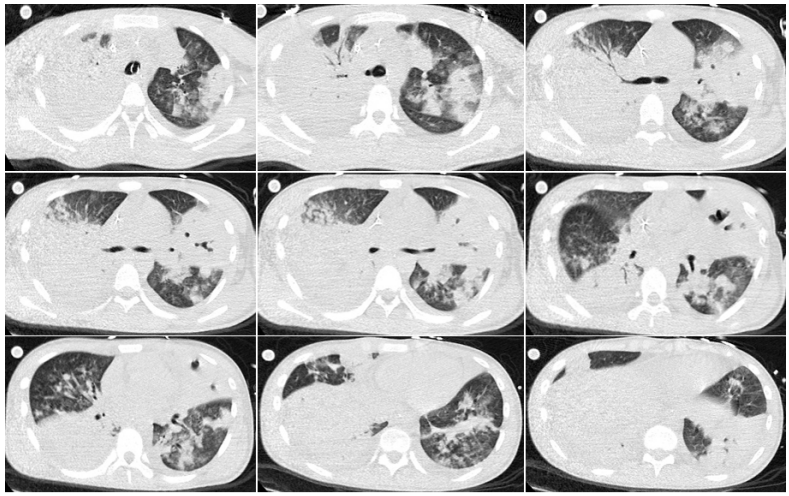

糖皮质激素的使用在其他病种中也被认为是IPA的危险因素,在重症流感中也不例外,有研究表明入ICU前系统性应用大剂量糖皮质激素是继发IAA的独立危险因素。除了重症流感,患者可能还会合并其他基础疾病,尤其是可以影响患者免疫状态的基础疾病,可能也是IAPA的危险因素。病例1::男,15岁,学生;主因“发热、干咳16天,加重伴呼吸困难8天”入院。既往体健,无基础病。入中日医院MICU时间为2018年1月16日,死亡时间为2018年1月26日。患者16天前(2017年12月30日)出现发热,体温39.0℃,伴干咳、咽痛。8天前(2018年1月7日)出现呼吸困难。血气分析示Ⅱ型呼吸衰竭,WBC 24.1×109/L,NE% 90%,PCT 3.3 ng/ml。不断升级抗细菌治疗,效果不佳:头孢曲松→亚胺培南、阿奇霉素、利奈唑胺。7天前(2018年1月8日)确诊乙流,加用帕拉米韦+奥司他韦。2天前(2018年1月13日):血GM试验测值增高,痰培养烟曲霉,诊断IAPA,加用伏立康唑。2018年1月15日转入中日医院呼吸与危重症医学科MICU。2018年1月8日胸部CT(起病1周余)提示气压伤非常严重,以及沿气道分布的斑片和小结节。此时的影像学提示曲霉感染已经显而易见(图1),但尚未得到病原学证据的支持,因此外院当时并未予抗真菌治疗,延迟抗真菌治疗也是导致患者预后不良的重要原因之一。1月15日(转入中日医院MICU后)气管镜检查,镜下可见气道狭窄和黏膜充血水肿均较明显,表面大量白苔,触之易出血(图2)。此时除了曲霉感染,BALF病原学还发现合并了CRAB感染。患者影像学快速进展,1月15日胸部CT显示双肺弥漫性沿支气管血管束分布的结节影、斑片影、厚壁空洞及片状实变(图3)。1月22日胸部CT显示双肺病变明显进展,结节、斑片融合为大面积实变影(图4)。最终患者因CRAB血流感染导致感染性休克,后期又并发脓毒性心肌病,最终去世。病例2::女,65岁,退休。间断干咳伴发热10天,加重伴呼吸困难4天。既往2型糖尿病史35年,使用精蛋白生物合成人胰岛素注射液(预混30R)治疗,血糖波动在7~8 mmol/L。患者入ICU时间为2018年2月4日,出ICU时间为2018年4月19日。10天前(2018年1月25日)“感冒”后出现干咳,伴发热,体温最高37.8℃。7天前(2018年1月28日),血常规:WBC 12.49×109/L,NEU% 87.5%,LYM% 7%,予莫西沙星。1月30日复查血常规:WBC 23.88×109/L,NEU% 91.5%,LY% 4.6%,调整抗生素为头孢噻肟+莫西沙星。4天前(1月31日)呼吸困难加重,SpO2(未吸氧)88%,复查血常规:WBC 37.04×109/L,NEU% 93.7%,LYM% 1.7%,PCT 1.79 ng/ml,痰涂片可见真菌孢子及菌丝。3天前(2月1日)咳痰费力,SpO2降至71%,开放气道吸痰过程中心率降至32次/min,立即心肺复苏,气管插管球囊辅助通气,约12 min患者自主心率恢复,接呼吸机辅助呼吸,经气道可吸出大量黄色黏痰,痰流感病毒核酸阳性。1月31日胸部CT示:沿支气管血管束分布的斑片和实变影(图5)。气管镜下可见充血、水肿,曲霉特征性假膜相对较少(图6)。

2月13日复查胸部CT(抗真菌治疗14天)显示影像学较前好转(图7)。患者病程中也经历了院感、肺外脏器支持等,病情最终好转出院。(1)一般情况:流感合并曲霉感染患者, 男性居多, 年龄大, 基础病情更加严重, 伴有免疫抑制因素(例如: 肿瘤、免疫抑制剂、激素)。(2)起病时间较早(入ICU早期),入ICU至IAPA诊断的平均时间<72小时(3天),短于COVID-19相关肺曲霉病(CAPA)4~13天,流感至IAPA诊断时间为(13±7)天。(3)临床症状/体征不典型:IAPA的临床表现无特异性,可表现为发热、咳嗽、呼吸困难、病情加重且对现有治疗无效。部分患者可能出现咳黑褐色痰或咯血,并且有致死性大咯血风险。CAPA和COVID-19相关肺毛霉病(CAPM)患者发展为重症需入住ICU的比例更高。此外,患者常合并呼吸衰竭/ARDS、急性肾损伤(AKI)、感染性休克。(4)实验室及影像学检查:实验室检查有一项比较重要的提示,IAPA患者可能会因为炎症反应强烈而导致WBC非常高,但PCT一般不会明显升高,淋巴细胞常明显降低。影像学表现有其特点(如前所述)。(5)独立危险因素:ICU早期WBC明显增高(>10×109/L)、入ICU后应用激素、CT特征表现(多发结节、空洞)是IAPA的独立危险因素。但仍需大样本量、多中心的病例对照研究进一步验证。从上述两个病例可以发现,由于患者的症状、体征、实验室检查大部分不特异,且常被伴发的流感及混合的细菌感染所掩盖,因此IAPA的早期诊断较困难。微生物学依据是诊断IAPA的金标准,而在拿到微生物学证据之前,影像学和气管镜检查可以帮助我们寻找蛛丝马迹,在临床上具有重要意义及提示作用,有助于早期诊断。因此,熟悉其表现尤为重要。(1)微生物学证据:2020年欧洲医学真菌学协会/国际人类和动物真菌学学会(ECMM/ISHAM)发布的关于CAPA的定义及共识声明中提到的检测方法以及cut off值可供参考,包括:①BALF直接镜检阳性、BALF培养/PCR阳性,血GM/LFA>0.5,BALF-GM/LFA≥1;②血浆/血清/全血PCR阳性≥2次;③单次BALF PCR阳性且CT<36;④单次血浆/血清/全血PCR阳性,且单次BALF-PCR阳性(不要求CT值)。(2)CT表现:CT在IAPA的早期诊断中具有重要的提示意义。病变沿支气管血管束分布;合并曲霉感染患者有明显的气道受累,包括气道壁增厚、气道狭窄,以及树芽征;典型的病变性质是结节和斑片,空洞及新月征不多见,但有特异性;大片实变影也相对特异,且提示预后差。(3)气管镜下表现:气管镜也是一种非常重要的早期诊断IAPA的手段,可以发现气管镜下典型的假膜。除了观察气道病变的特点及范围,还可以获得高质量的下呼吸道标本,有助于提高真菌培养阳性率,获取及动态监测BALF-GM试验结果。此外,气管镜还能够进行痰液引流。对于气道病变非常严重或局限的患者,气管镜还可以进行气道内给药。值得一提的是,来自欧洲7个国家和美国以及中国台湾等地的29名专家提出了IAPA诊断专家共识,2023年已发表在Intensive Care Medicine 杂志上,将IAPA分为曲霉菌性气管支气管炎及侵袭性肺曲霉病,高度强调了气管镜的重要性,无论是气管镜镜下表现还是气管镜获取BALF标本进行GM试验或真菌培养都是共识中的重要条目,可能有助于IAA的早期诊断。